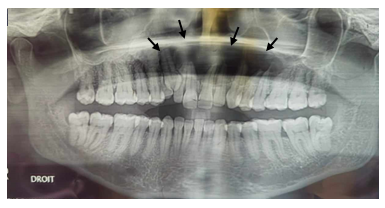

A 43-year-old female patient was referred to our oral surgery department for evaluation of a well-defined radiolucent lesion in the anterior maxillary region, incidentally discovered during a radiological examination (Figure 1). The patient was in good general health, with no significant medical or family history.

Figure 1 Panoramic radiograph: image of radiolucent cystic appearance, well limited, extended of 12 to 26.

Clinical examination revealed a mild, soft swelling in the left vestibular region without any signs of pain or infection, raising suspicion of vestibular cortical bone perforation. All teeth in the affected region were vital and free from caries. A fine needle aspiration was performed, yielding a whitish, caseous material rich in keratin, effectively ruling out an inflammatory cyst. Orthopantomogram imaging revealed a well-defined radiolucency extending from the maxillary incisor region to the contralateral right premolar-molar area.